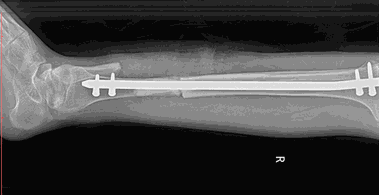

If the patient does not heal well, we must consider the fracture that goes to delayed union, nonunion, and understand when to intervene.

• Nonunion Fractures